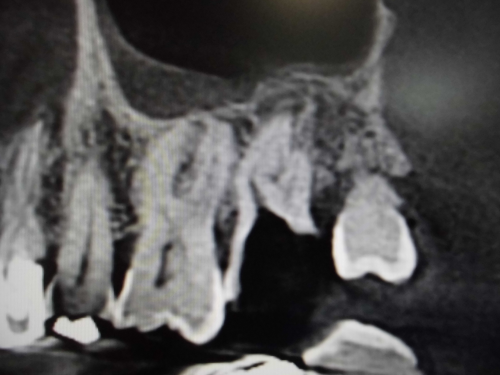

上顎洞との位置関係が確認できます。

CTでは近心の第二根管も確認できます。

原因が頬側近心根とわかりました。上顎洞粘膜が肥厚しているのもわかります。